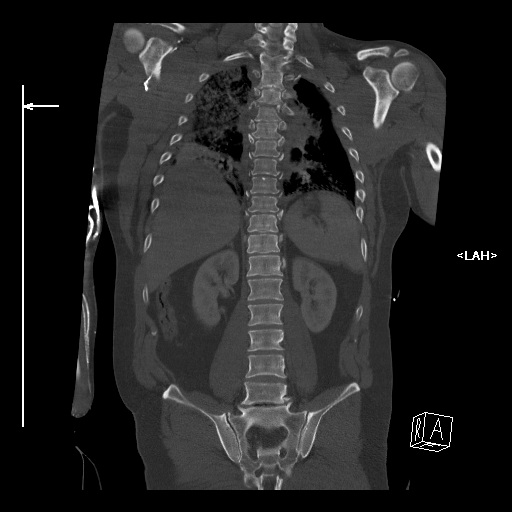

----------- следущая часть -----------

Вложение в формате HTML было извлечено&hellip;

URL: http://weborto.net:8080/pipermail/ortho/attachments/20121017/f0f92842/attachment-0001.htm

Вложение не в текстовом формате было извлечено&hellip;

Имя     : коронарная1.jpg

Тип     : image/jpeg

Размер  : 58423 байтов

Описание: отсутствует

Url     : http://weborto.net:8080/pipermail/ortho/attachments/20121017/f0f92842/attachment-0002.jpg